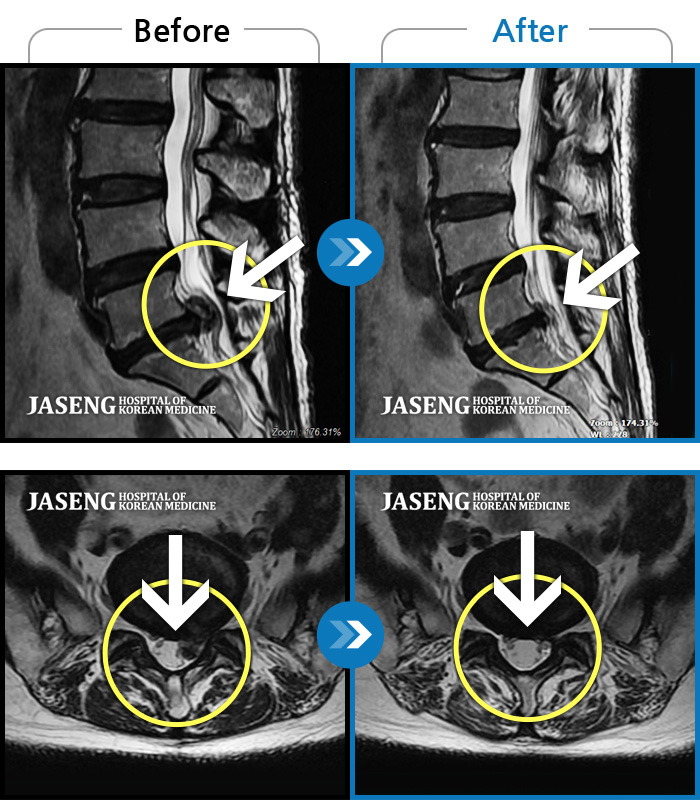

MRI ġ

MRI ũ ʸ Ȯϼ.

ȯںп Ǹ ǿ ԿǾ, ο ġ ۿ Ƿ ġḦ Ͻñ ٶϴ.